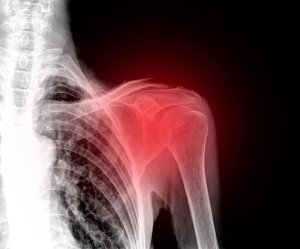

Omuz ağrısı çok rahatsız edici ve engelleyici bir durumdur çünkü omuz eklemleri çevrenizle verimli bir şekilde etkileşime geçmenizi sağlarlar.

Ağrıya, şişliğe ve tutulmaya sebep olan farklı sakatlanma türleri vardır. Ayrıca tıbbi bir tedaviden geçmezseniz kronik şişkinlikle baş etmek zorunda kalabilirsiniz.

Patolojiler ve Omuz Ağrısının En Yaygın Sebepleri

Omuz ağrısıyla ilişkili en yaygın hastalıklar şunlardır: